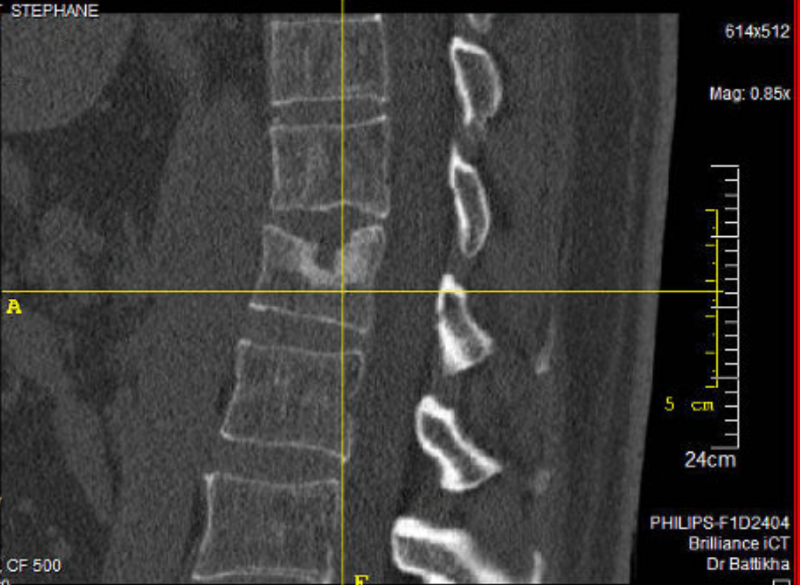

Ça ne te consolera certes pas mais voilà à quoi ressemblait ma colonne vertébrale en l'an 2001 à 51 ans, aujourd'hui à 69 ans je bosse toujours comme saisonnier because la retraite suffit pas. Courage !

vos colonnes vertébrales sont encore plus pourries que nos side car, et là c'est pas facile à restaurer, mais je crois que le gagnant est omar celo avec la vertèbre toute bouffée au croisement des deux lignes , on dirait qu'une souris est venue bouffer un morceau pendant la nuit !!!!